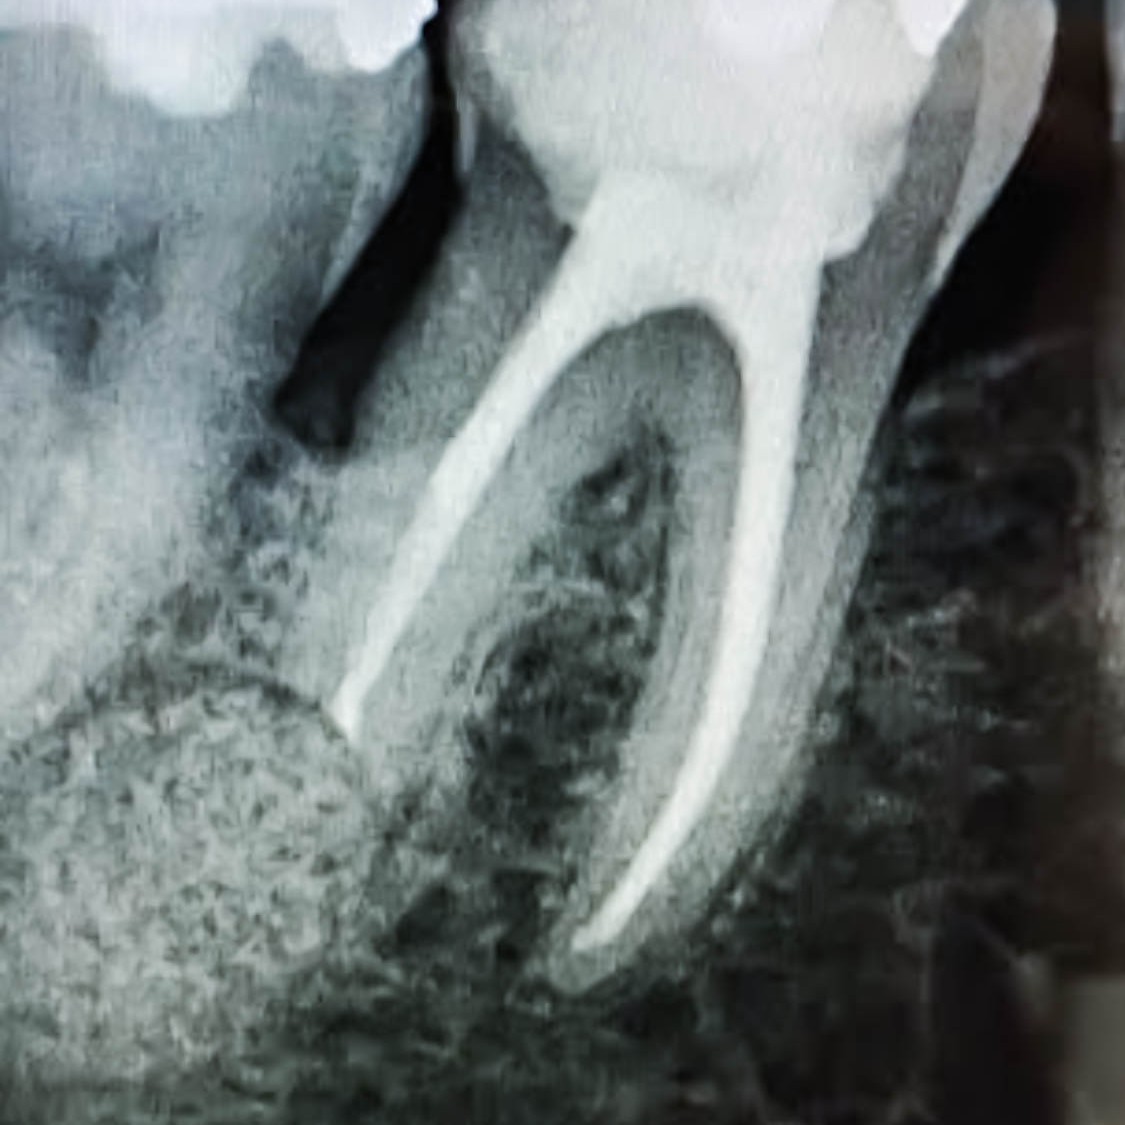

Wurzelkanalbehandlung / Endodontie

Bei starken pulpitischen Schmerzen oder radiologischen Auffälligkeiten kann eine Wurzelkanalbehandlung nötig sein. Durch das Einleiten einer solchen Behandlung können Zähne erhalten werden, die unter anderen Umständen gezogen werden müssten. Ob eine Wurzelkanalbehandlung möglich und sinnvoll ist, wird immer als Einzelfall mit dem Behandler besprochen und abgewogen.

3D Röntgen DVT

Für radiologische Untersuchungen mit speziellen Fragestellung im Dental- als auch HNO- Bereich, bietet das DVT (digitale Volumentomographie) das genaueste Aufnahmeverfahren. Die 3D Röntgendarstellung kann sowohl zur Fokussuche bei Beschwerden, Wurzelkanalbehandlungen als auch bei chirurgischen Planungen genutzt werden. Für eine chirurgische Behandlungsplanung mit Implantaten ist dieses Verfahren der neueste Standard.